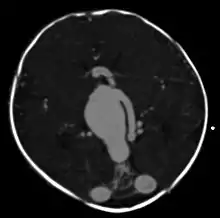

Axial image from computerized tomography angiogram showing arteriovenous communication in

vein of Galen malformation

Vein of Galen thrombosis from ventricular puncture, not to be mistaken for an aneurysmal malformation

A cerebral AVM diagnosis is established by neuroimaging studies after a complete neurological and physical examination.[5][12] Three main techniques are used to visualize the brain and search for an AVM: computed tomography (CT), magnetic resonance imaging (MRI), and cerebral angiography.[12] A CT scan of the head is usually performed first when the subject is symptomatic. It can suggest the approximate site of the bleed.[3] MRI is more sensitive than CT in the diagnosis, and provides better information about the exact location of the malformation.[12] More detailed pictures of the tangle of blood vessels that compose an AVM can be obtained by using radioactive agents injected into the blood stream. If a CT is used in conjunction with an angiogram, this is called a computerized tomography angiogram; while, if MRI is used it is called magnetic resonance angiogram.[3][12] The best images of a cerebral AVM are obtained through cerebral angiography. This procedure involves using a catheter, threaded through an artery up to the head, to deliver a contrast agent into the AVM. As the contrast agent flows through the AVM structure, a sequence of X-ray images are obtained.[12]